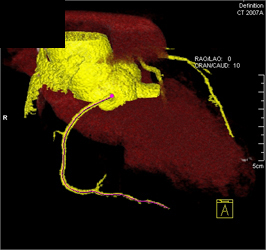

CASE NUMBER 672

Plaque on LAD